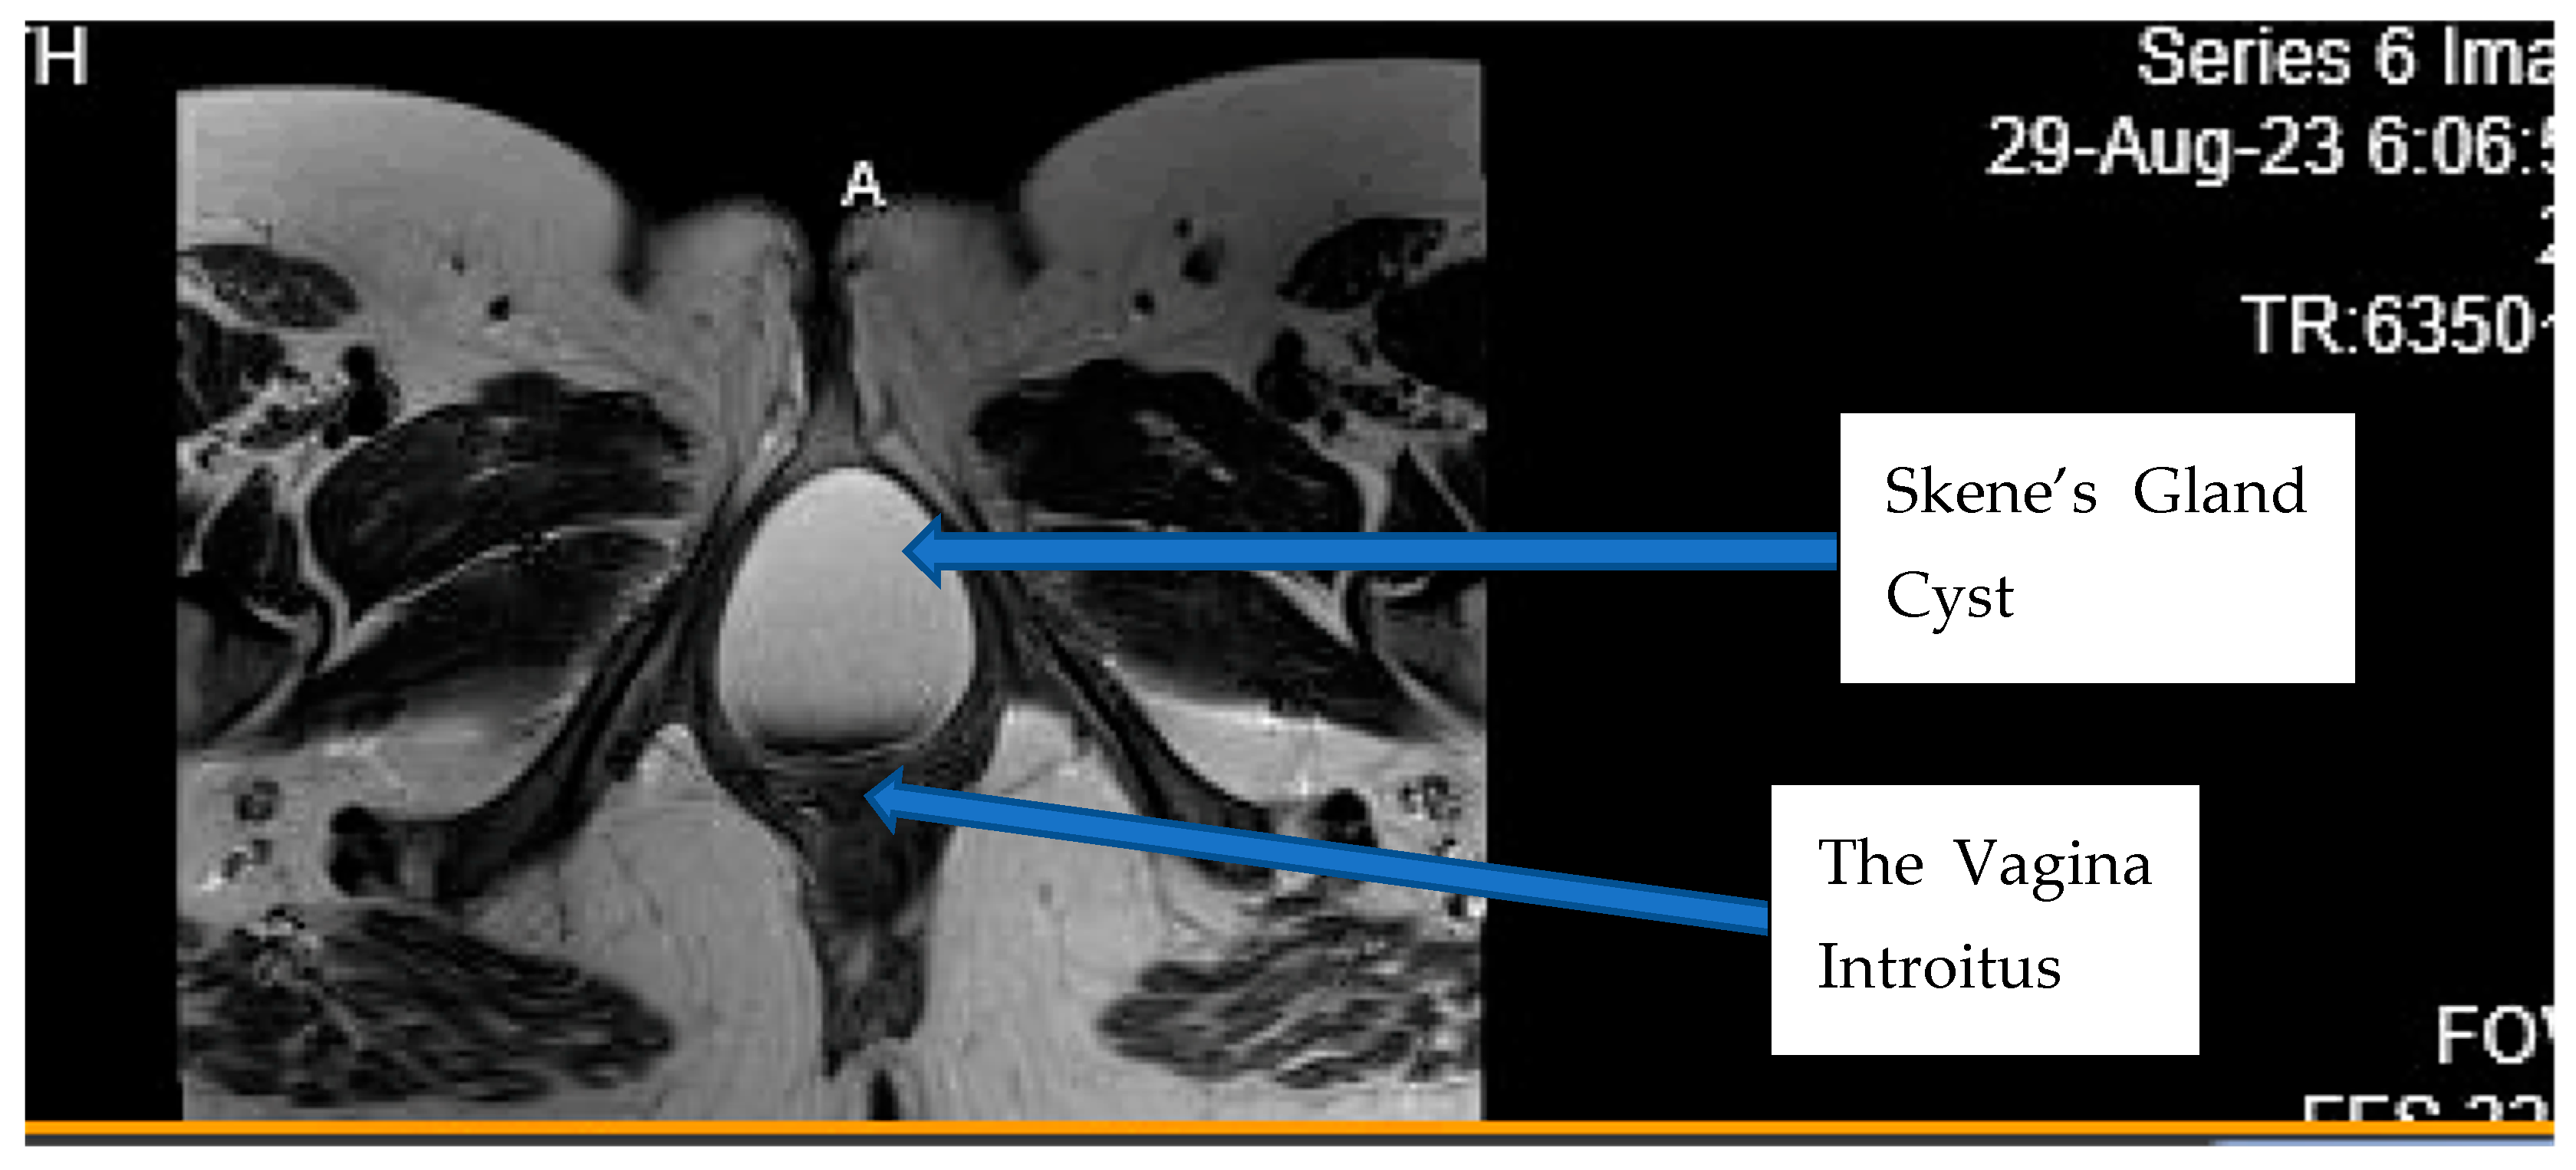

Clinical Findings: The patient’s primary obstetrician and gynecologist performed a pelvic exam and ultrasound, and her physician was concerned because of the large size of the mass, which appeared to be obstructing the vaginal introitus and compressing the external urethral meatus (Figure 2 and Figure 3). The fetal anatomy ultrasound performed did not show any evidence of significant fetal anomalies. She was immediately sent to the emergency department for further evaluation, where a pelvic MRI without contrast was performed to assess the origin of the mass and its extent (Figure 4 and Figure 5).

Diagnostic Assessment: The MRI found a lesion that abuts and indents the posterior wall of the urethra (Figure 2). It did not arise or connect to the urethra. It was a benign-appearing cystic lesion between the posterior wall of the urethra and the anterior wall of the vagina. The cystic lesion measured approximately 9 cm × 7 cm × 6 cm. It appeared to be a cyst with hemorrhagic or proteinaceous debris with a thin, smooth wall (Figure 2). There was no surrounding inflammation or tissue infiltration.

Figure 2. Transverse MRI image without contrast of maternal pelvis showing the Skene’s gland posterior to the urethra. A = Labia Majora.